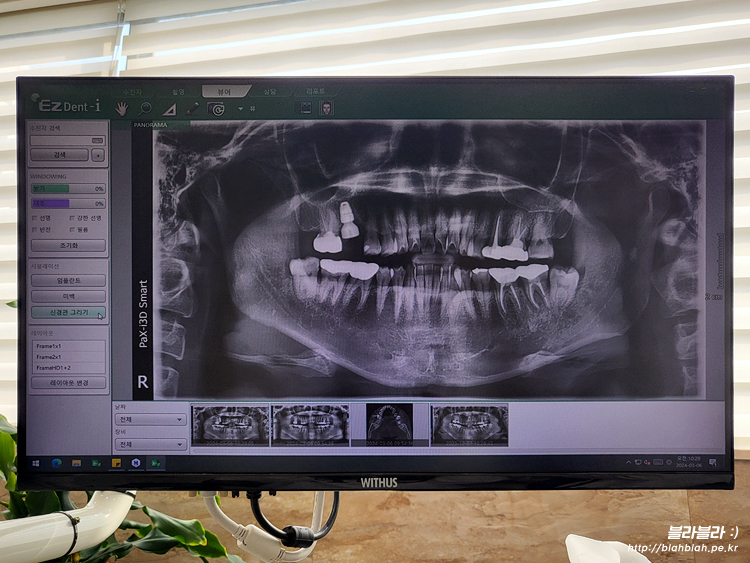

그리고 3월 6일 대망의 임플란트 식립날

병원에 방문하니 식립할 임플란트 종류 확인하고

임플란트 동의서 작성하고 파노라마 CT 촬영 후

임플란트를 심고나서 주변에 2바늘정도 꼬매고 끝!

마지막으로 다시 파노라마 촬영하고